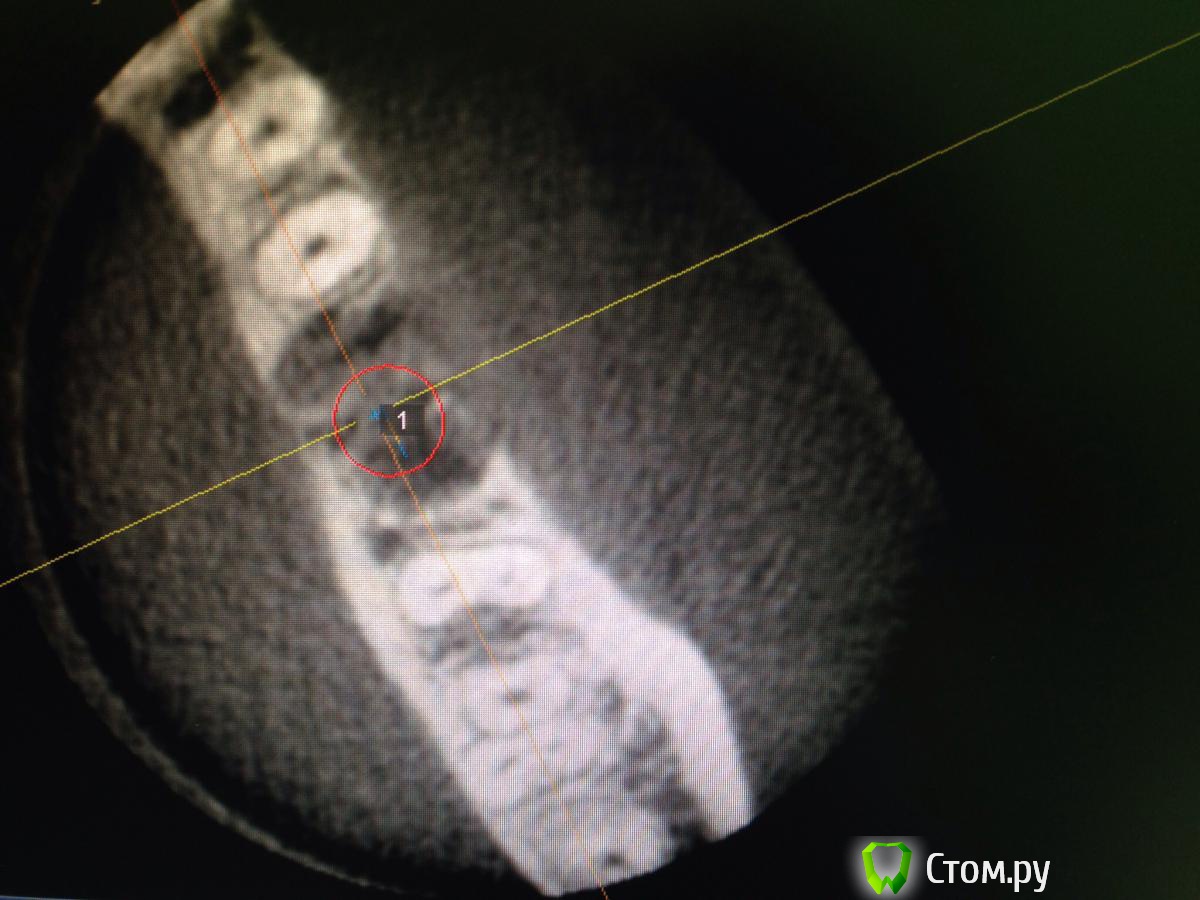

diesel87 Опубликовано 10 февраля, 2014 Поделиться Опубликовано 10 февраля, 2014 Планируется установка винта в области удаленного 3 месяца назад 36 зуба, размером 4,8*12; вот срезы кт, винт планирую в такой позиции, волнует костная пластика, нужна ли она и где именно и не слишком ли глубоко будет стоять винт по отношению к соседним зубам? Ссылка на комментарий

syrovovec Опубликовано 10 февраля, 2014 Поделиться Опубликовано 10 февраля, 2014 12 у вас в плотную к каналу,при такой постановке у знакомый доктор получил онемение.на следующий день выкрутил на пол витка.продолжения не знаю 1 Ссылка на комментарий

Sahan Опубликовано 10 февраля, 2014 Поделиться Опубликовано 10 февраля, 2014 Учитывая что Вам нужно на 1 мм утопить имплантат, а на крайнем фото до канала осталось около 2 мм, 12 мм будет впритык к каналу. Что , как писал коллега выше, может боком вылезти. Ссылка на комментарий

kriokov Опубликовано 10 февраля, 2014 Поделиться Опубликовано 10 февраля, 2014 крутите 4.2 х 10, если кореец, субкрестально на 1 мм, и по переферии кости больше останется, и до канала нормально.В лунке минерализации нет, прошло только 3 мес. Если почувствуете, что пилотник очень легко на всю глубину прошел, дальше можно остеотомами МИсовскими, Ссылка на комментарий